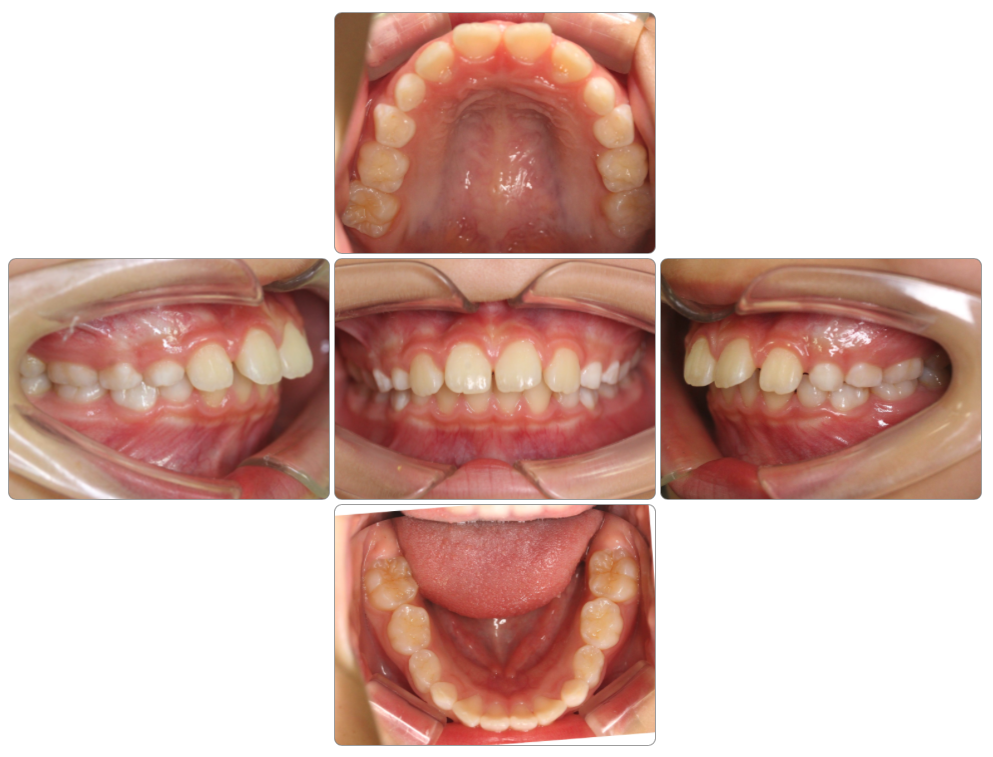

叢生の治療例

Before

after

| 初診時 | 9歳8ヵ月 |

| 治療期間 | 1年半 |

| 費用 | ¥550,000・調整料¥5,500/月 |

| 使用装置 | マイオブレイス |

| リスクと副作用 | |

| 原因と考察 | 頭位が上がった姿勢になっているために舌が口蓋(上顎)に触れていません。このため口蓋の広がりが悪く歯並びが小さくなっているようです。マイオブレイスと共に正しい姿勢で生活できるようになることでその後の後戻りリスクが下がると思います。 |